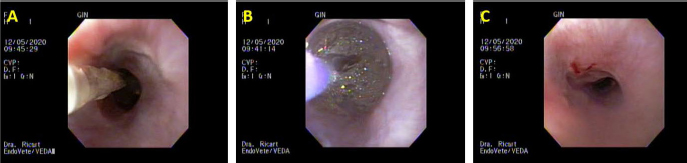

Fig. 2. Third day of endoluminal dilatation and second triamcinolone injection. (A) Initial dilatation with a Boston Scientific CRE balloon of 12 mm. (B) Balloon inflated during the maneuver; note there is no evidence of bleeding or tearing of the mucosa. (C) Macroscopic evaluation of mucosal damage after the third dilatation of the day; mild tearing is observed.